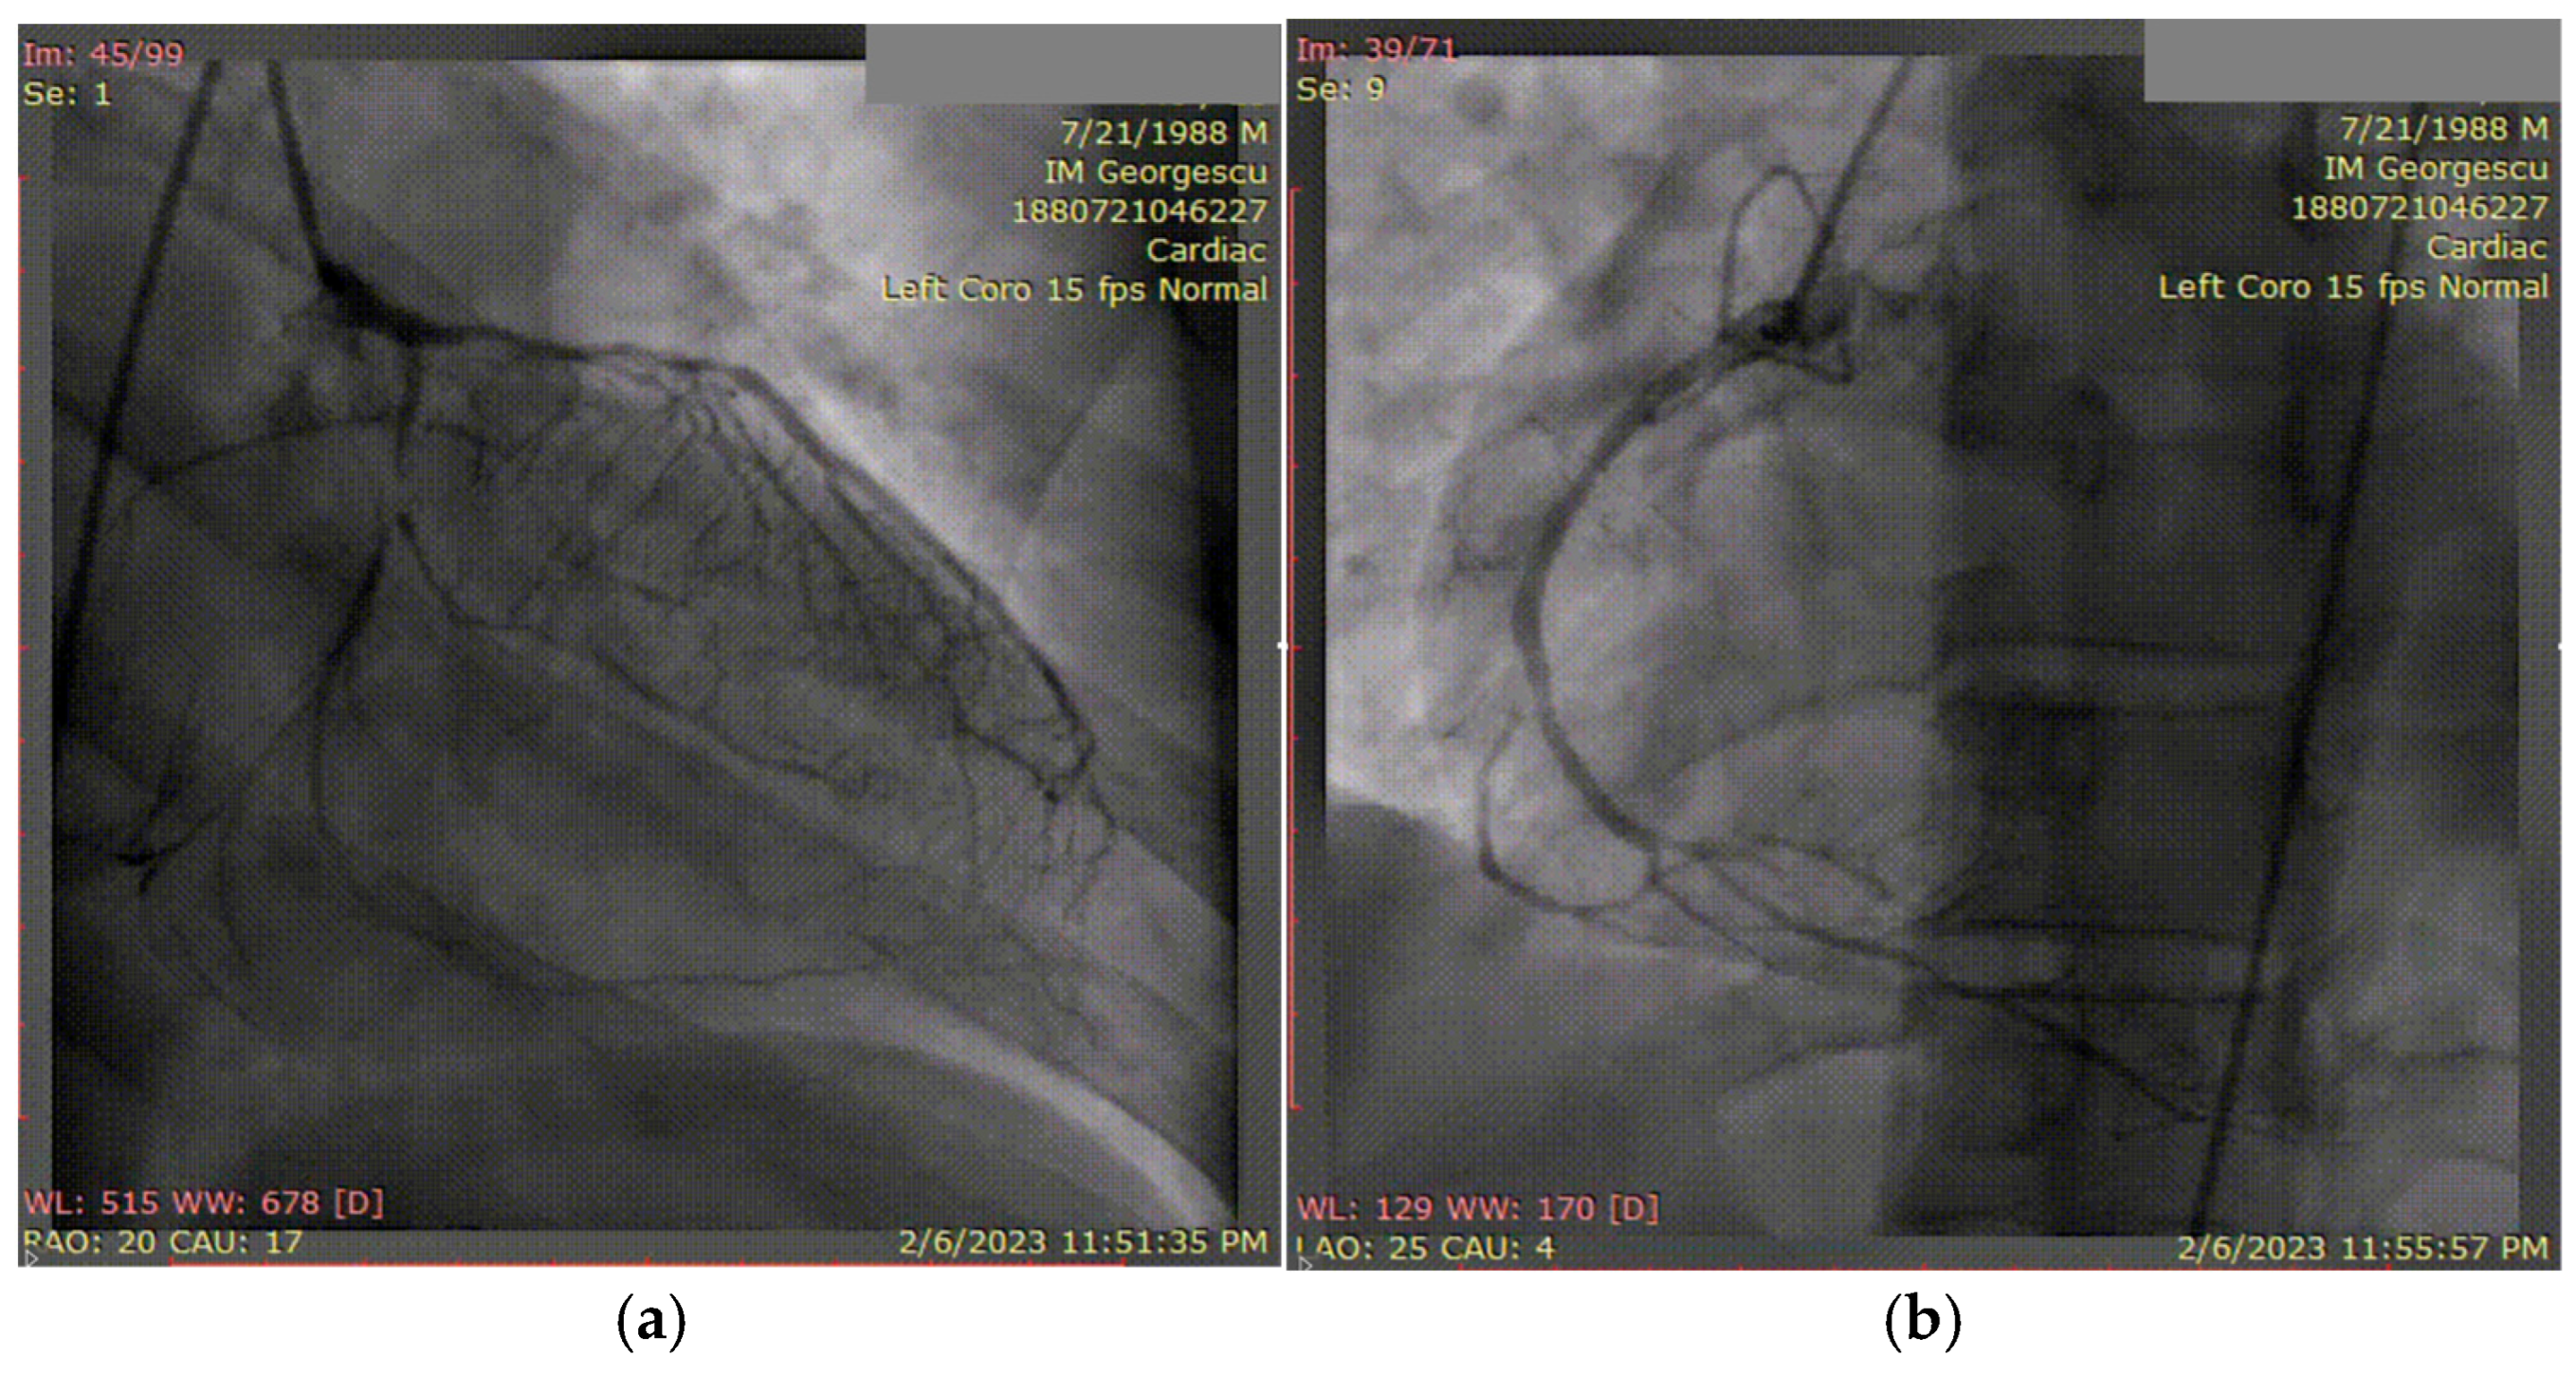

3.1. Case 1

3.2. Case 2

3.3. Case 3

3.4. Case 4